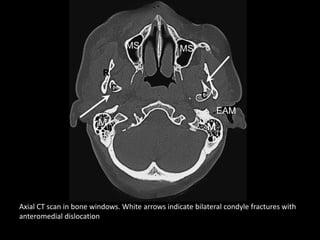

Axial CT scan in bone windows. White arrows indicate bilateral condyle fractures with

anteromedial dislocation